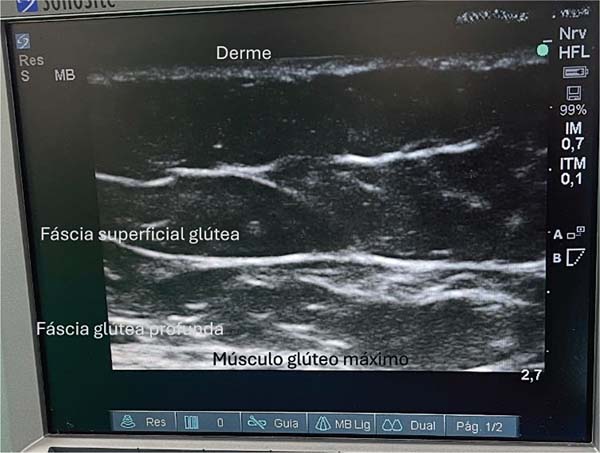

Anatomia da região

Classicamente, essa região é caracterizada pela presença de duas fáscias e duas camadas de tecido subcutâneo com gordura. Na avaliação ultrassonográfica, é possível visualizar uma fáscia mais fina e elástica, e outra, mais espessa. A fáscia mais fina divide o tecido subcutâneo em duas camadas, e forma a região onde a gordura será depositada (►Fig. 1).

As estruturas anatômicas da região glútea são visualizadas em um iPad (Apple Inc.) de décima geração, via ultrassom Wi-Fi. Esse exame permite a identificação das seguintes camadas: pele, derme, gordura superficial, fáscia glútea superficial (ou fáscia de Scarpa), gordura profunda e fáscia glútea profunda. Esta última está localizada logo acima da musculatura, e deve ser evitada a todo custo. Idealmente, o enxerto de gordura deve ser depositado na camada de gordura profunda. A preservação da fáscia glútea profunda, aliada a incisões menores do que 1 cm, previne a migração da gordura para o plano muscular.9,10